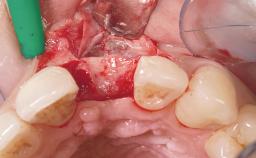

Late Flapless Placement of an Implant in a Maxillary Left Central Incisor Site

A 39-year-old male patient presented with a chief complaint of discomfort and gingival discoloration around his maxillary left central incisor. He was in good general health and was a non-smoker. His past dental history was significant because of the traumatic fracture of tooth 21 in a sporting accident at age 13. Initial dental treatment included endodontic therapy and a full-coverage restoration. The patient became symptomatic 5 years later, when structural failure of the tooth resulted in the dislodgment of the crown. Endodontic retreatment, apical surgery, and post-and-core restoration were performed.

| Bone Augmentation | Horizontal|Staged |

| Augmentation Materials | Xenogenous|Membrane |